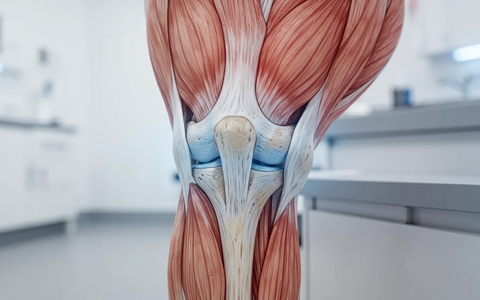

Arthrose ist eine der häufigsten Gelenkerkrankungen. Der fortschreitende Knorpelabbau verursacht Schmerzen und schränkt die Bewegung ein. Lange rieten Ärzte zur Schonung – heute setzt die moderne Therapie auf gezielte Aktivität. Isometrisches Training, bei dem Muskeln ohne Gelenkbewegung angespannt werden, rückt dabei in den Fokus.

Bei isometrischen Übungen bleibt das Gelenk in einer Position. Der Muskel arbeitet statisch, wie beim Unterarmstütz (Plank) oder Wandsitzen. Diese Kontraktion ohne Bewegung kräftigt die Muskulatur effektiv, ohne schmerzhafte Reibung im Gelenk zu erzeugen.

Eine starke Muskulatur entlastet und stabilisiert das Gelenk. Das kann Schmerzen direkt reduzieren. Eine systematische Übersichtsarbeit bestätigt: Isometrisches Training verbessert bei Kniearthrose die Schmerzsituation und die Gelenkfunktion.

Der größte Vorteil ist die minimale Belastung. Weil keine Bewegung stattfindet, entfallen die schmerzhaften Phasen dynamischer Übungen. Das macht isometrische Kräftigung zur idealen Einstiegsmethode, besonders bei akuten Schmerzen oder fortgeschrittener Arthrose.